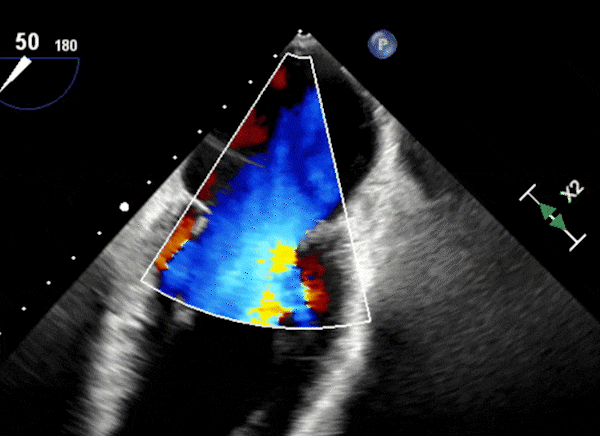

心脏超声示左室增大,二尖瓣2、3区脱垂伴重度反流(腱索断裂),Carpentier分型Ⅱ型,典型Barlow综合征表现;二尖瓣开放面积5.0cm²,3区瓣环内径31mm,前叶长22mm、后叶17mm,前叶收缩期关闭瓣体部分呈拱形突向左房腔,瓣膜游离缘对合欠佳,可见腱索断裂,长度9mm;2区瓣环内径32mm,前叶长22mm、后叶10mm,前后叶均可脱垂;三尖瓣重度反流。CDFI示瓣口重度偏心性反流,反流束沿主动脉后壁走行,肺静脉收缩期可见反向频谱。

术前反流

图片